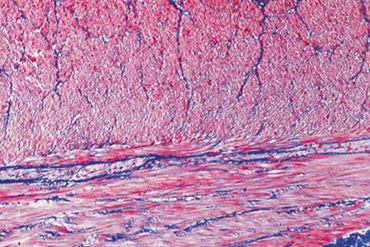

Slide, Smooth Muscle, sec.